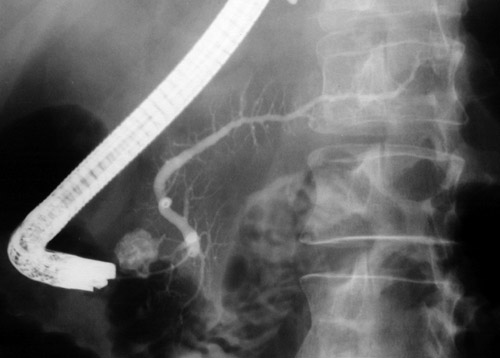

| With injection of contrast material via endoscopic retrograde pancreatography (ERCP), contrast can be seen filling a pancreatic pseudocyst in the region of the pancreatic head. Note also that the pancreatic duct is slightly dilated and tortuous, typical of changes from inspissated ductal secretions with chronic alcoholism that predisposes to pancreatitis and pseudocyst formation. |